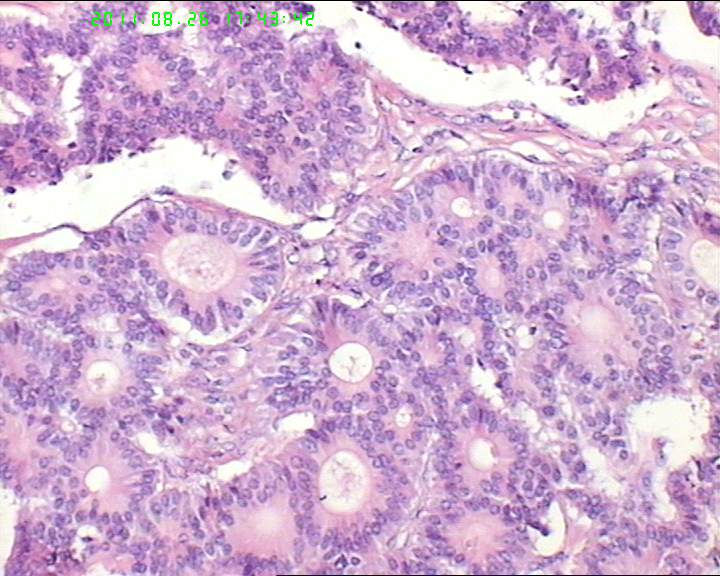

76岁女性卵巢巨大囊性肿物

卵巢肿物,大小18*14*10cm

,切面灰黄色,中央见一囊腔,12*4cm大小,未见内容物,内壁光滑。囊壁厚约4cm。

支持细胞瘤,伴性索分化的生殖细胞肿瘤,类癌,转移性腺癌

考虑支持细胞瘤或者类癌,要免疫组化鉴别

卵巢囊性颗粒细胞瘤

恶性肿瘤,可能是一般的上皮性肿瘤,也可能是神经内分泌肿瘤,需要免疫组化。排除一下颗粒细胞瘤。